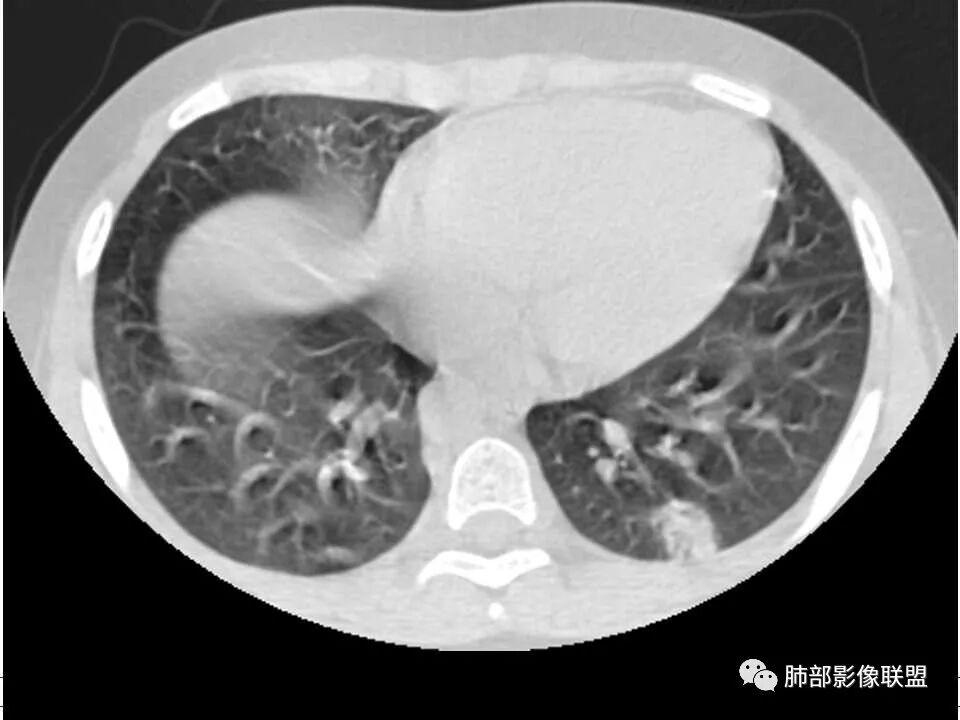

患者儿童,因右下肢疼痛伴肿胀14天就诊。病程中有发热及伴随症状。膝关节MRI提示右侧膝关节及右髌骨髁异常信号影,右膝髌上囊及关节腔内少量积液。胸部CT:双肺胸膜下多发结节影,部分结节空洞形成,且结节周围可见血管集束征。综合考虑血源性脓毒性肺栓塞、坏死性肺炎。右侧骨髓炎、血播性金葡菌肺炎,鉴别其他特殊感染及血管炎。

发热,下肢肿胀骨髓水肿,骨髓炎可能;双肺多发结节,部分空洞,左下肺胸膜下楔形阴影,考虑感染性病变,肺梗死;上腔静脉、奇静脉增宽,肝大,考虑股部深静脉拴子进入体循环及肺动脉,综上考虑下肢骨髓炎,深静脉脓毒栓子,肺部感染并肺栓塞

儿童,发热,急性起病,右下肢骨水肿,两肺弥漫性病变,伴囊,胸膜下分布,部分呈楔形,血道分布,符合金葡菌感染,脓毒肺栓塞

2.双肺多发片影,随机分布,多空洞或囊腔,胸膜下多楔形影,气道未见受累等等符合脓毒血症影像学表现,尤其是金葡。

是肺栓塞的一种少见类型,但病情严重,其特征为含有病原体的栓子脱落后随血流进入肺血管系统导致肺栓塞(或梗死 ) 和局灶性肺脓肿。国内报道的 SPE 较少,且为个案报道或小样本数的报道。SPE 诊断依靠临床、微生物学及影像学的证据。SPE 诊断标准,总结如下:

1. 多发胸膜下外周结节、< 3 cm 的楔形影和滋养血管征 CT 表现;